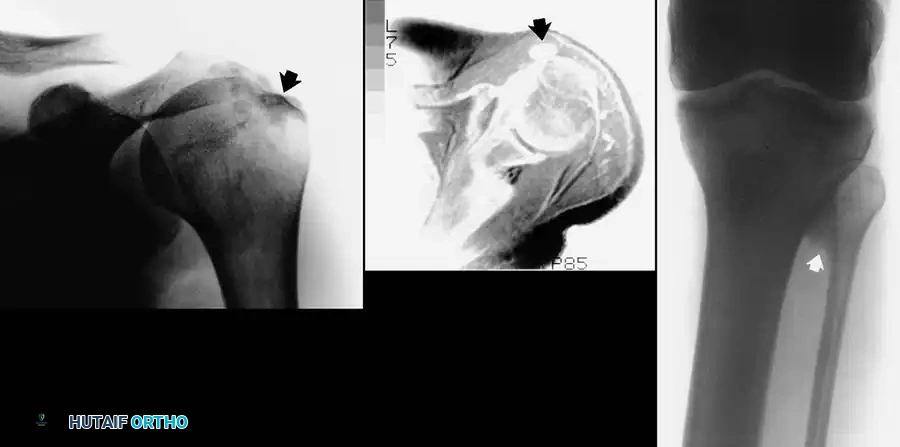

Image

Fig. 24-7: (A) Painful calcification of the anterior deltoid. (B) MRI demonstrating localization of the calcium deposit in the deltoid muscle. (C) Calcification of the proximal tibiofibular articulation resulting in peroneal nerve entrapment in a professional athlete.